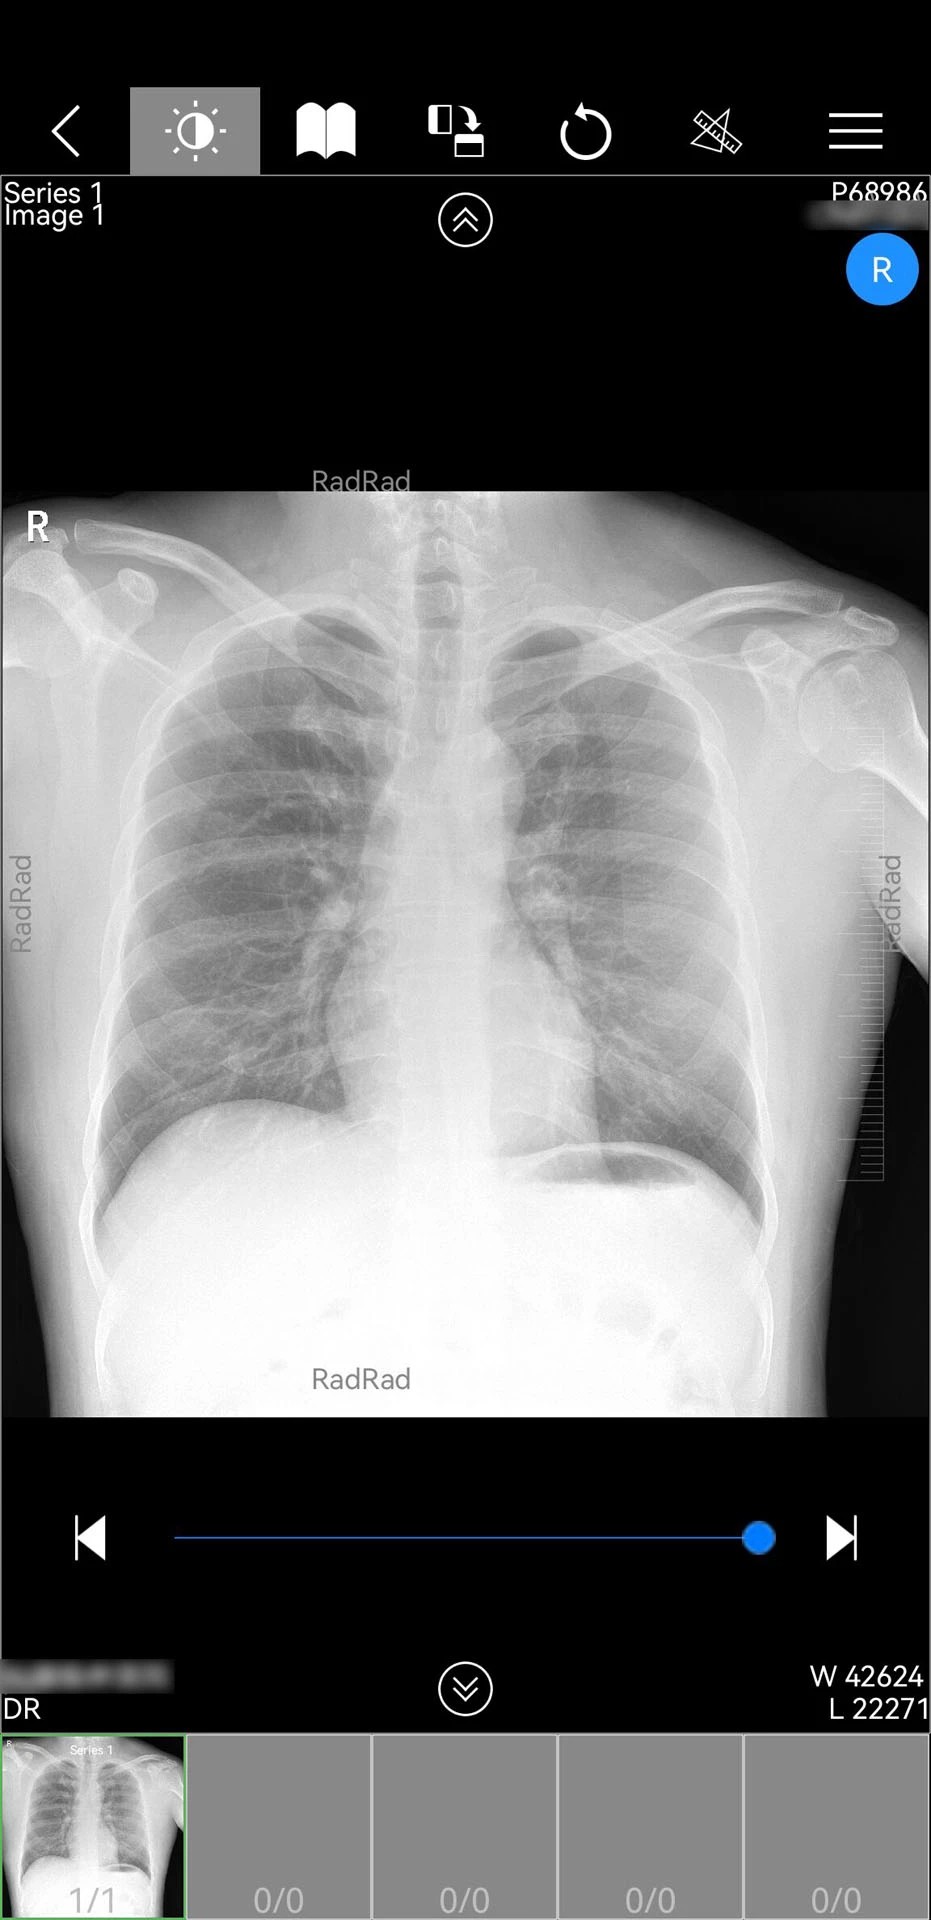

1. 全场景影像支持:支持DICOM格式原始影像解析,兼容CT、MRI、X光等多模态数据,提供窗宽窗位调节、三维重建等高级影像处理功能,医生可自由缩放、旋转影像进行多角度观察。

2. 极简操作设计:主界面采用“功能卡片+手势操作”模式,医生可通过左右滑动切换患者列表,双击影像快速放大细节,长按标记重点区域。例如,放射科医生在阅片时,单指滑动即可连续查看多层影像,双指捏合可调整观察视角。

1. 影像调阅流程:医生登录后,通过“患者列表”选择目标病例,系统自动从云服务器下载加密影像包。解密后,影像以时间轴形式排列,支持按检查类型(如CT平扫、增强扫描)或身体部位(如头部、胸部)筛选。例如,神经外科医生可快速定位患者最近一次的脑部MRI影像,对比术前术后变化。